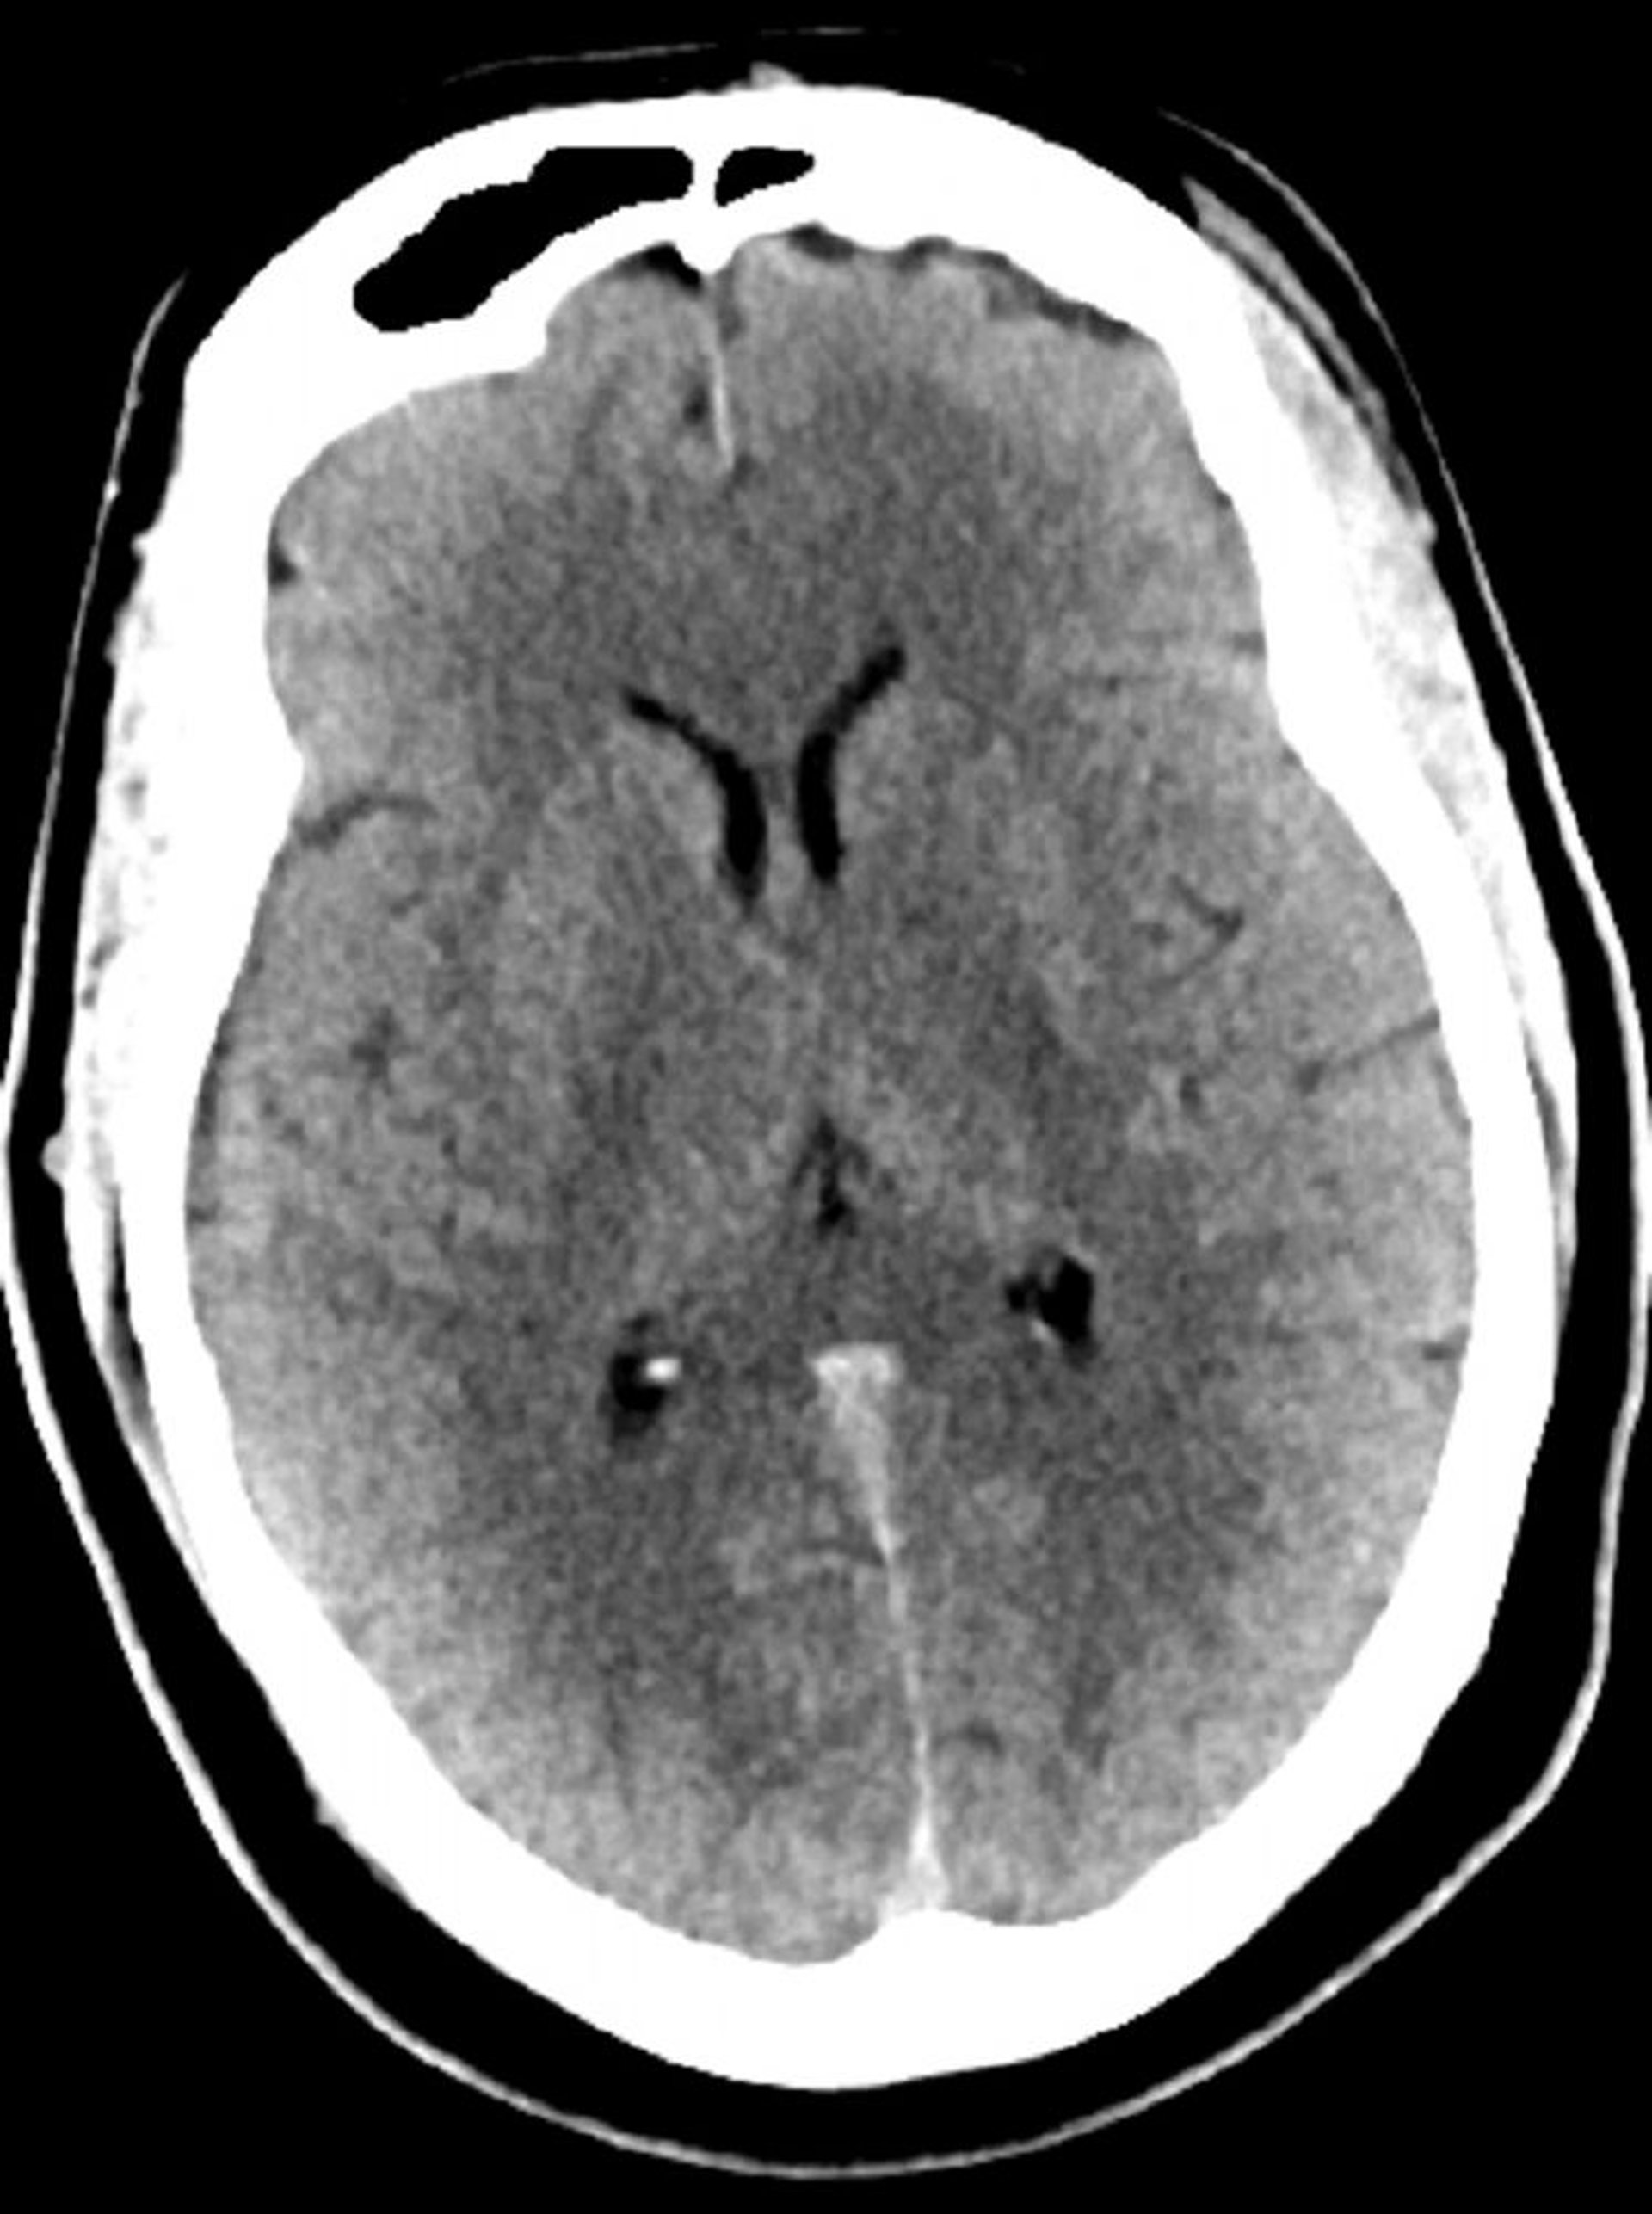

TC de crânio normal (adulto, idade 30) – – Diapositivo 5

Essa é uma TC normal da cabeça de um adulto jovem com 30 anos. Não há líquido ou hemorragia intra ou extra axial. A diferenciação cinza-branco é preservada. O tamanho ventricular e o padrão dos sulcos parecem normais.